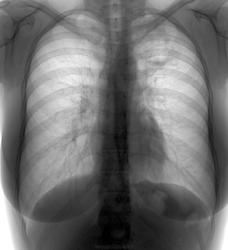

Женщина около 40 лет. Профоосмотр. особых жалоб не предьявляет.

Что скажете?

Полость, с небольшим уровне жидкости в 1 сегменте справа, вокруг полости, в окружающей легочной ткани видится также "непотребство". На мой взгляд, надо верхушки порезать.

Похоже на порок развития бронхов с воспалением. К твс сердце не лежит, все-таки на  БК проверить надо, ну и динамика все остальное подскажет...

Вполне могут быть дизонтогенетические бронхоэктазы.

Пригласил барышню на беседу...оказывается все это тянется еще с 15 лет....

Да все бы хорошо....но как Вам динамика за эти шесть лет? И что скажете о перифокальной инфильтрации кпереди от полостей?